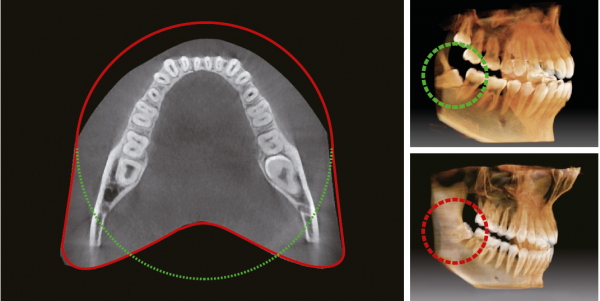

Анатомическое поле сканирования FOV10x8,5 = FOV 12×9

Инновационная форма объема Pax-i3D 10х8,5 (12X9) обеспечивает сканирование в форме зубной дуги и показывает весь зубной ряд, в отличии от других аппаратов с аналогичным по размеру FOV. Обычно FOV10x8.5см достаточно для сканирования 38 и 48 зубов. Тем не менее, когда они лежат на боку, существует высокая вероятность того, что они не попадут в зону сканирования. FOV в форме зубной дуги устраняет эту вероятность, показывая скрытую область.